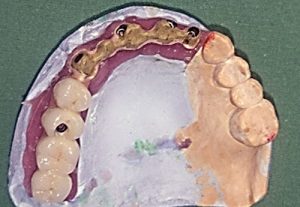

3. PHASE – fabrication of temporary solution